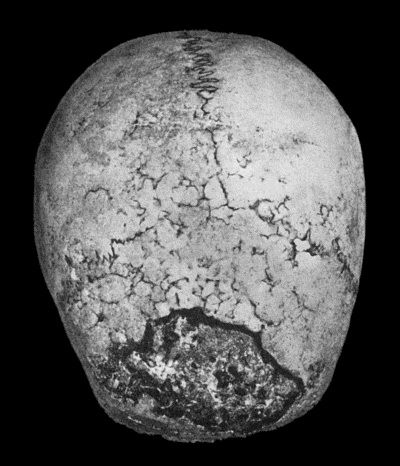

461 130.Syphilitic Disease of Skull

463 131.Syphilitic Hyperostosis and Sclerosis of Tibia